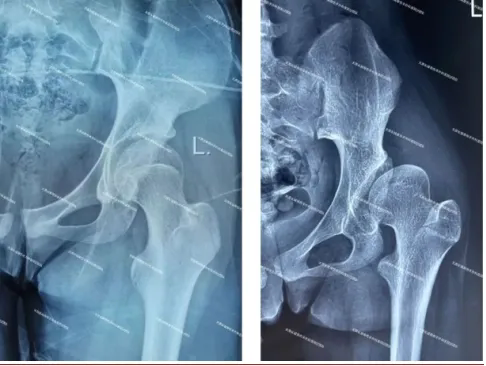

(正常髖關(guān)節(jié)X線(左圖)顯示髖臼對(duì)股骨頭的包容良好;發(fā)育不良髖關(guān)節(jié)X線(右圖)顯示髖臼對(duì)股骨頭的包容不足。)